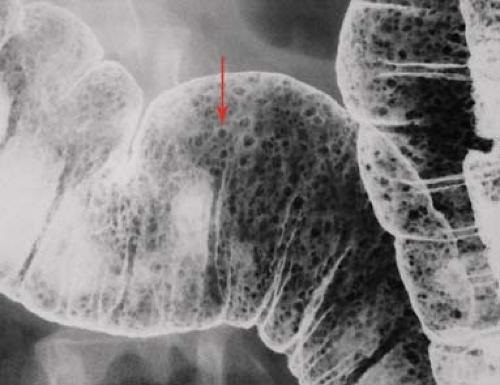

Image radiologique d'une

polyp du colon sigmoide . Ápect en forme de champignon

du polyp situe au face anterieur du colon avec

pedicule ( fleche rouge ) . Image de lavement du

colon en double de contrast . |